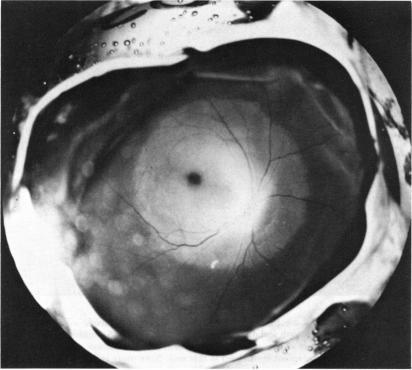

Three major pathologic processes caused by light in the primate retina: a search for mechanisms.

Trans Am Ophthalmol Soc. 1982;80:517-79.